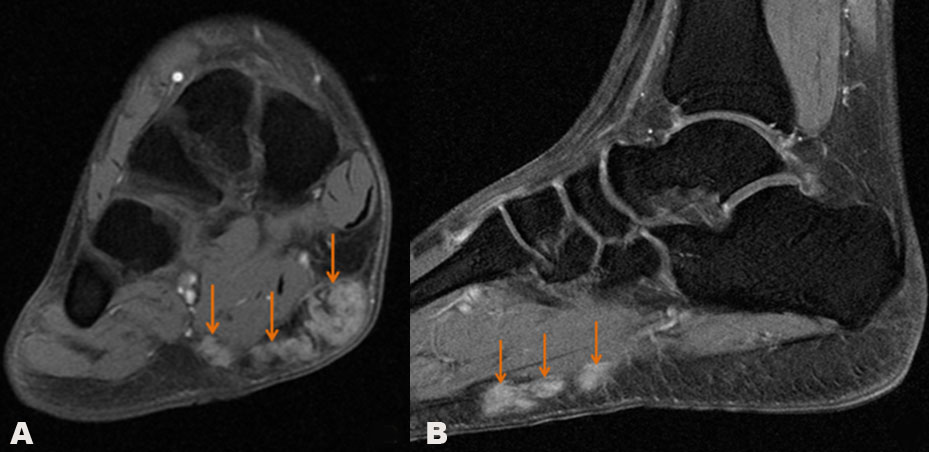

It shows a multinodular mass thickening in the distal part of the superficial plantar aponeurosis regarding the flexor digitorum brevis of the right midfoot, the mass is slightly hypointense compared to the muscle on T1 weighted (Figure 1A), with digitations of a low signal along with the mass. On proton density sequence after fat saturation, the mass is in hyperintense signal relative to muscles and persistently low-signal digitations (Figure 1B), with heterogeneous enhancement after gadolinium injection (Figure 2). There was no associated aponeuropathy.

Figure 1: MRI of the left foot in axial section in T1-weighted sequence (a) and in sagittal section in proton density weighting after saturation of the fat (b), the images demonstrate a multinodular thickening in the distal part of the plantar fascia in T1-weighted hyposignal and hypersignal in DP, the lesion presents multilobulated and regular outline, it bombs in the underlying muscle and skin without signs of involvement.

Figure 2: MRI of the left foot in axial (a) and sagittal (b) sections in T1-weighted sequence with fat saturation and gadolinium injection, we notice an intense and heterogeneous enhancement of the lesion after gadolinium injection. The underlying muscle is respected.

Currently, MRI is the best modality for assessment of a plantar fibroma, it is useful for the mass characterization and evaluating its extension into the surrounding tissue. On the T1-weighted sequence, areas of dense collagen within the fibroma present a low signal intensity comparing to the muscle (Figure 1A), and on T2-weighted sequence it appears with low to intermediate signal intensity, lesions involving deeper structures demonstrate usually high signal intensity on T2-weighted images, and lesions with high collagen content present generally a low signal intensity appearance in T2-weighted images [8],[9].

We find typically a high intensity in proton density sequence after fat saturation (Figure 1B), and the contrast injection reveals variable enhancement that is often marked and heterogeneous (Figure 2) and may extend along the plantar aponeurosis [7],[10]. In a series of 15 patients, fibromatosis nodule was not enhanced for one case (7%), a mild enhancement was found in five cases (33%), and it was marked in nine (60%) [11]. Despite the cost, MRI is crucial in surgical planning by the determination of the margins of the lesion and its extension into adjacent structures, allowing for better surgical resection [7].